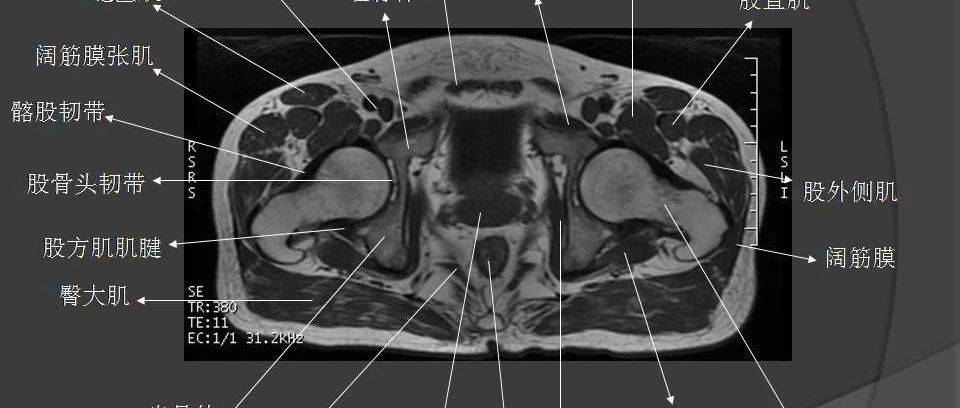

女性生殖系统ct,磁共振解剖

影像解剖丨盆腔